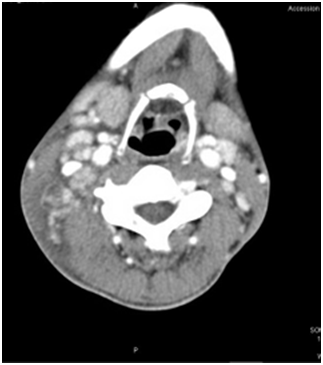

Blood tests revealed pancytopenia with normocytic normochromic anemia, leucopenia with significant neutropenia, and low platelets (Table 1). Serum LDH was more than 1000U/L with low serum haptoglobin (<4 milligrams per deciliter), indicating intravascular hemolysis. Serum electrolytes were normal, but liver enzymes were significantly elevated (Table 1). C-Reactive protein (45milligrams per liter) and Procalcitonin (0.29nanograms per milliliter) were mildly elevated. Electrocardiogram was normal, but chest radiographs showed bilateral pleural effusion (Figure 1). Peripheral smear showed mild normocytic normochromic anemia with few spherocytes and moderate rouleaux formation, leukopenia with neutropenia, and many pleomorphic, reactive and atypical lymphocytes (with irregular nuclei & abundant basophilic cytoplasm). Platelets were moderately reduced.Serological tests for common viral diseases such as cytomegalovirus (CMV), Epstein-Barr virus (EBV), Human Immunodeficiency Virus (HIV), and hepatitis; blood, urine, and stool cultures were negative. Sputum cultures grew respiratory tract flora and were negative for acid-fast bacilli. All workups for tuberculosis (TB) were negative, including quantiferon, sputum acid fast bacilli smear, culture and polymerase chain reaction (PCR). Antinuclear antibody (ANA), Anti – Smith's Antibody, and Anti RNP antibodies were positive, while Rheumatoid Factor (RF) was negative. Serum C3 and C4 were low. Flow cytometry from Bone Marrow biopsy and Lymph node aspiration biopsy was found to be negative for lymphoma and leukemia.

Figure 1 Chest X-Ray on admission showing bilateral pleural effusion.